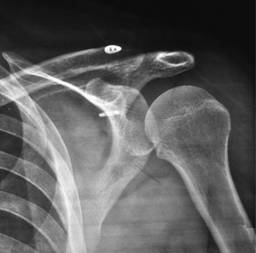

1) Técnica de Bosworth modificada. Es un método mínimamente invasivo, fue descrito en 1941 y consiste en la colocación de un tornillo cortical por lo general de 4.5 mm con arandela metálica de 11 mm desde la cortical superior de la clavícula hasta el proceso coracoideo en una dirección céfalo-caudal.15 La modificación de la técnica original como método complementario consiste en la colocación de dos clavillos tipo Kirschner 1.6 mm fijando el acromion a la clavícula en dirección latero-medial. Se retiran los clavillos Kirschner a la sexta semana y a la octava el tornillo, ambos de forma percutánea con anestesia local (Figura 1).